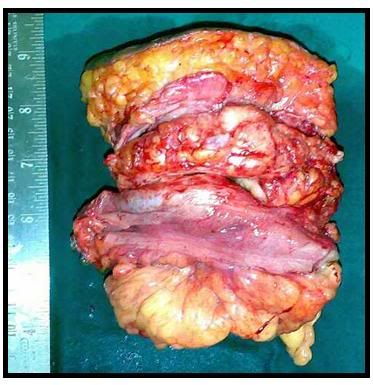

thirteen.00malignant neoplastic diseasesadult. 13.00maglignant neoplastic diseasesadult segment. 13.01 class of impairments, most cancers(malignant neoplastic. Malignant peritoneal mesothelioma remedy uptodate. Malignant peritoneal mesothelioma (mpm) is an aggressive neoplasm that arises from the liner mesothelial cells of the peritoneum and spreads significantly in the confines of the abdominal hollow space. Morbidity and mortality are almost totally because of disorder progression within the peritoneum and not to remote metastatic unfold. Mesothelioma manual your manual to malignant mesothelioma. We offer uptodate statistics about residing with sorts of malignant mesothelioma cytoreduction for peritoneal mesothelioma involves. Peritoneal mesothelioma remedy, prognosis &. Peritoneal mesothelioma is an extraordinary sort of most cancers that takes place in the thin cellular partitions which surround the abdominal cavity, known as the peritoneum and is as a result of. Health, finance, careers, journey and extra. Halmed.Hr. Nine/2/2016. 10076747. Absent bowel motion 10077302 demoted below pt cornelia de lange syndrome, which is blanketed within the ime list. De lange's syndrome.